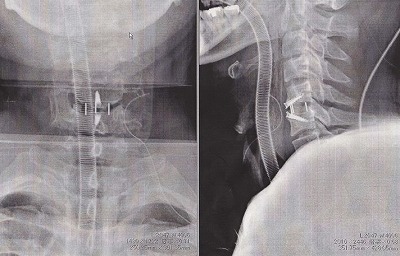

2,3年前に一度、右腕の力が入らなくなってしまい頸椎症性神経根症と診断され後方からの除圧術を受けました。

その病院に行くと頸椎症性脊髄症と診断されこのまま放っておくと歩けなく可能性もあると伝えられたのでオペを決心しました。

実際、リスクのあるオペだったので正直怖かったですが、先生方が「絶対に治してやる!」と勇気をくれたので安心して受けることができました。

無事にオペも成功し。現在は全身の怠さや足も引きずることもなく握力の方も以前に増して回復し身体が軽くなりました!